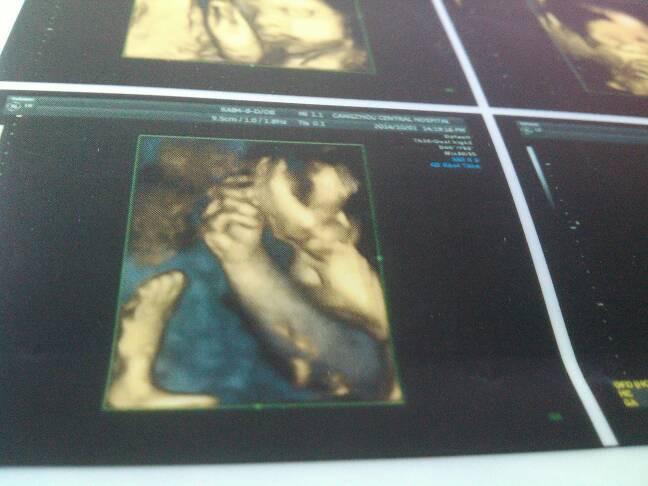

看看我宝的四维,像男孩还是女孩啊

呵呵…像妈妈就男孩几率大,像爸爸就女孩几率大!你应该更加清楚,我看像男宝,祝你如愿生女宝哦!

你好,根据这些图片不能判断是男是女,只能通过B超动态观察胎儿性别。

男孩吧呵呵